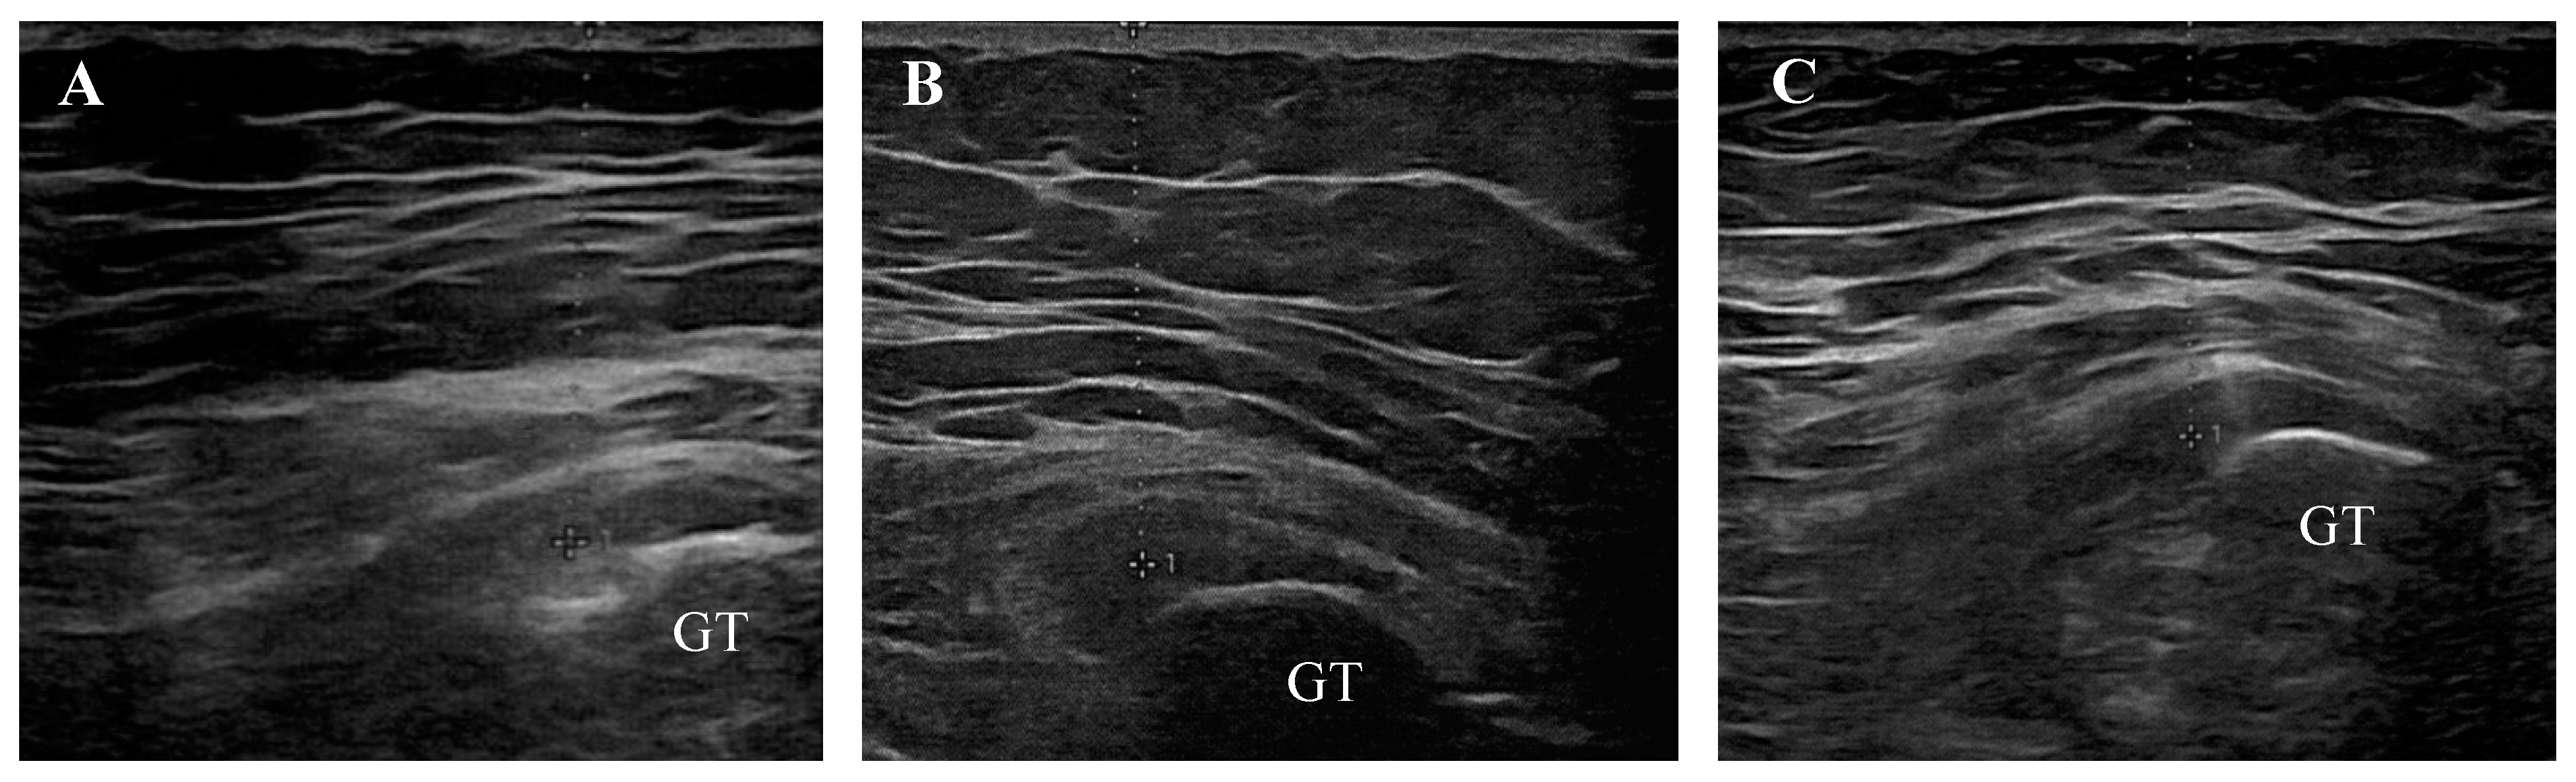

The descriptive data and clinical diagnosis according to the ultrasound examination of the sample are summarized in Table 3 and Figure 3.

Figure 3.

Transverse ultrasound views of pathological attachments of gluteus medius tendons onto the greater trochanter (GT). Representative images of tendinosis (A), enthesopathy (B), and enthesopathy accompanied by tendinosis (C).